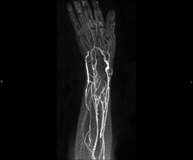

- Upper limb arterial MRI angiography

A non-invasive diagnostic test that involves studying the arteries of the shoulder girdle, arm, forearm and hand, obtaining high-definition anatomical images using an electromagnetic field and radio waves (with transmitter and receiver). The use of paramagnetic intravenous contrast (gadolinium) is essential. However, it is a radiation-free procedure. The quality of the images allows for 2D and 3D reconstructions. It is particularly recommended for patients with suspected vascular disease in both extremities, patients with vascular disease in both extremities as a vascular map prior to treatment (percutaneous or surgical), as a pre-surgical vascular map in patients with bone or muscle injuries requiring surgery, etc.